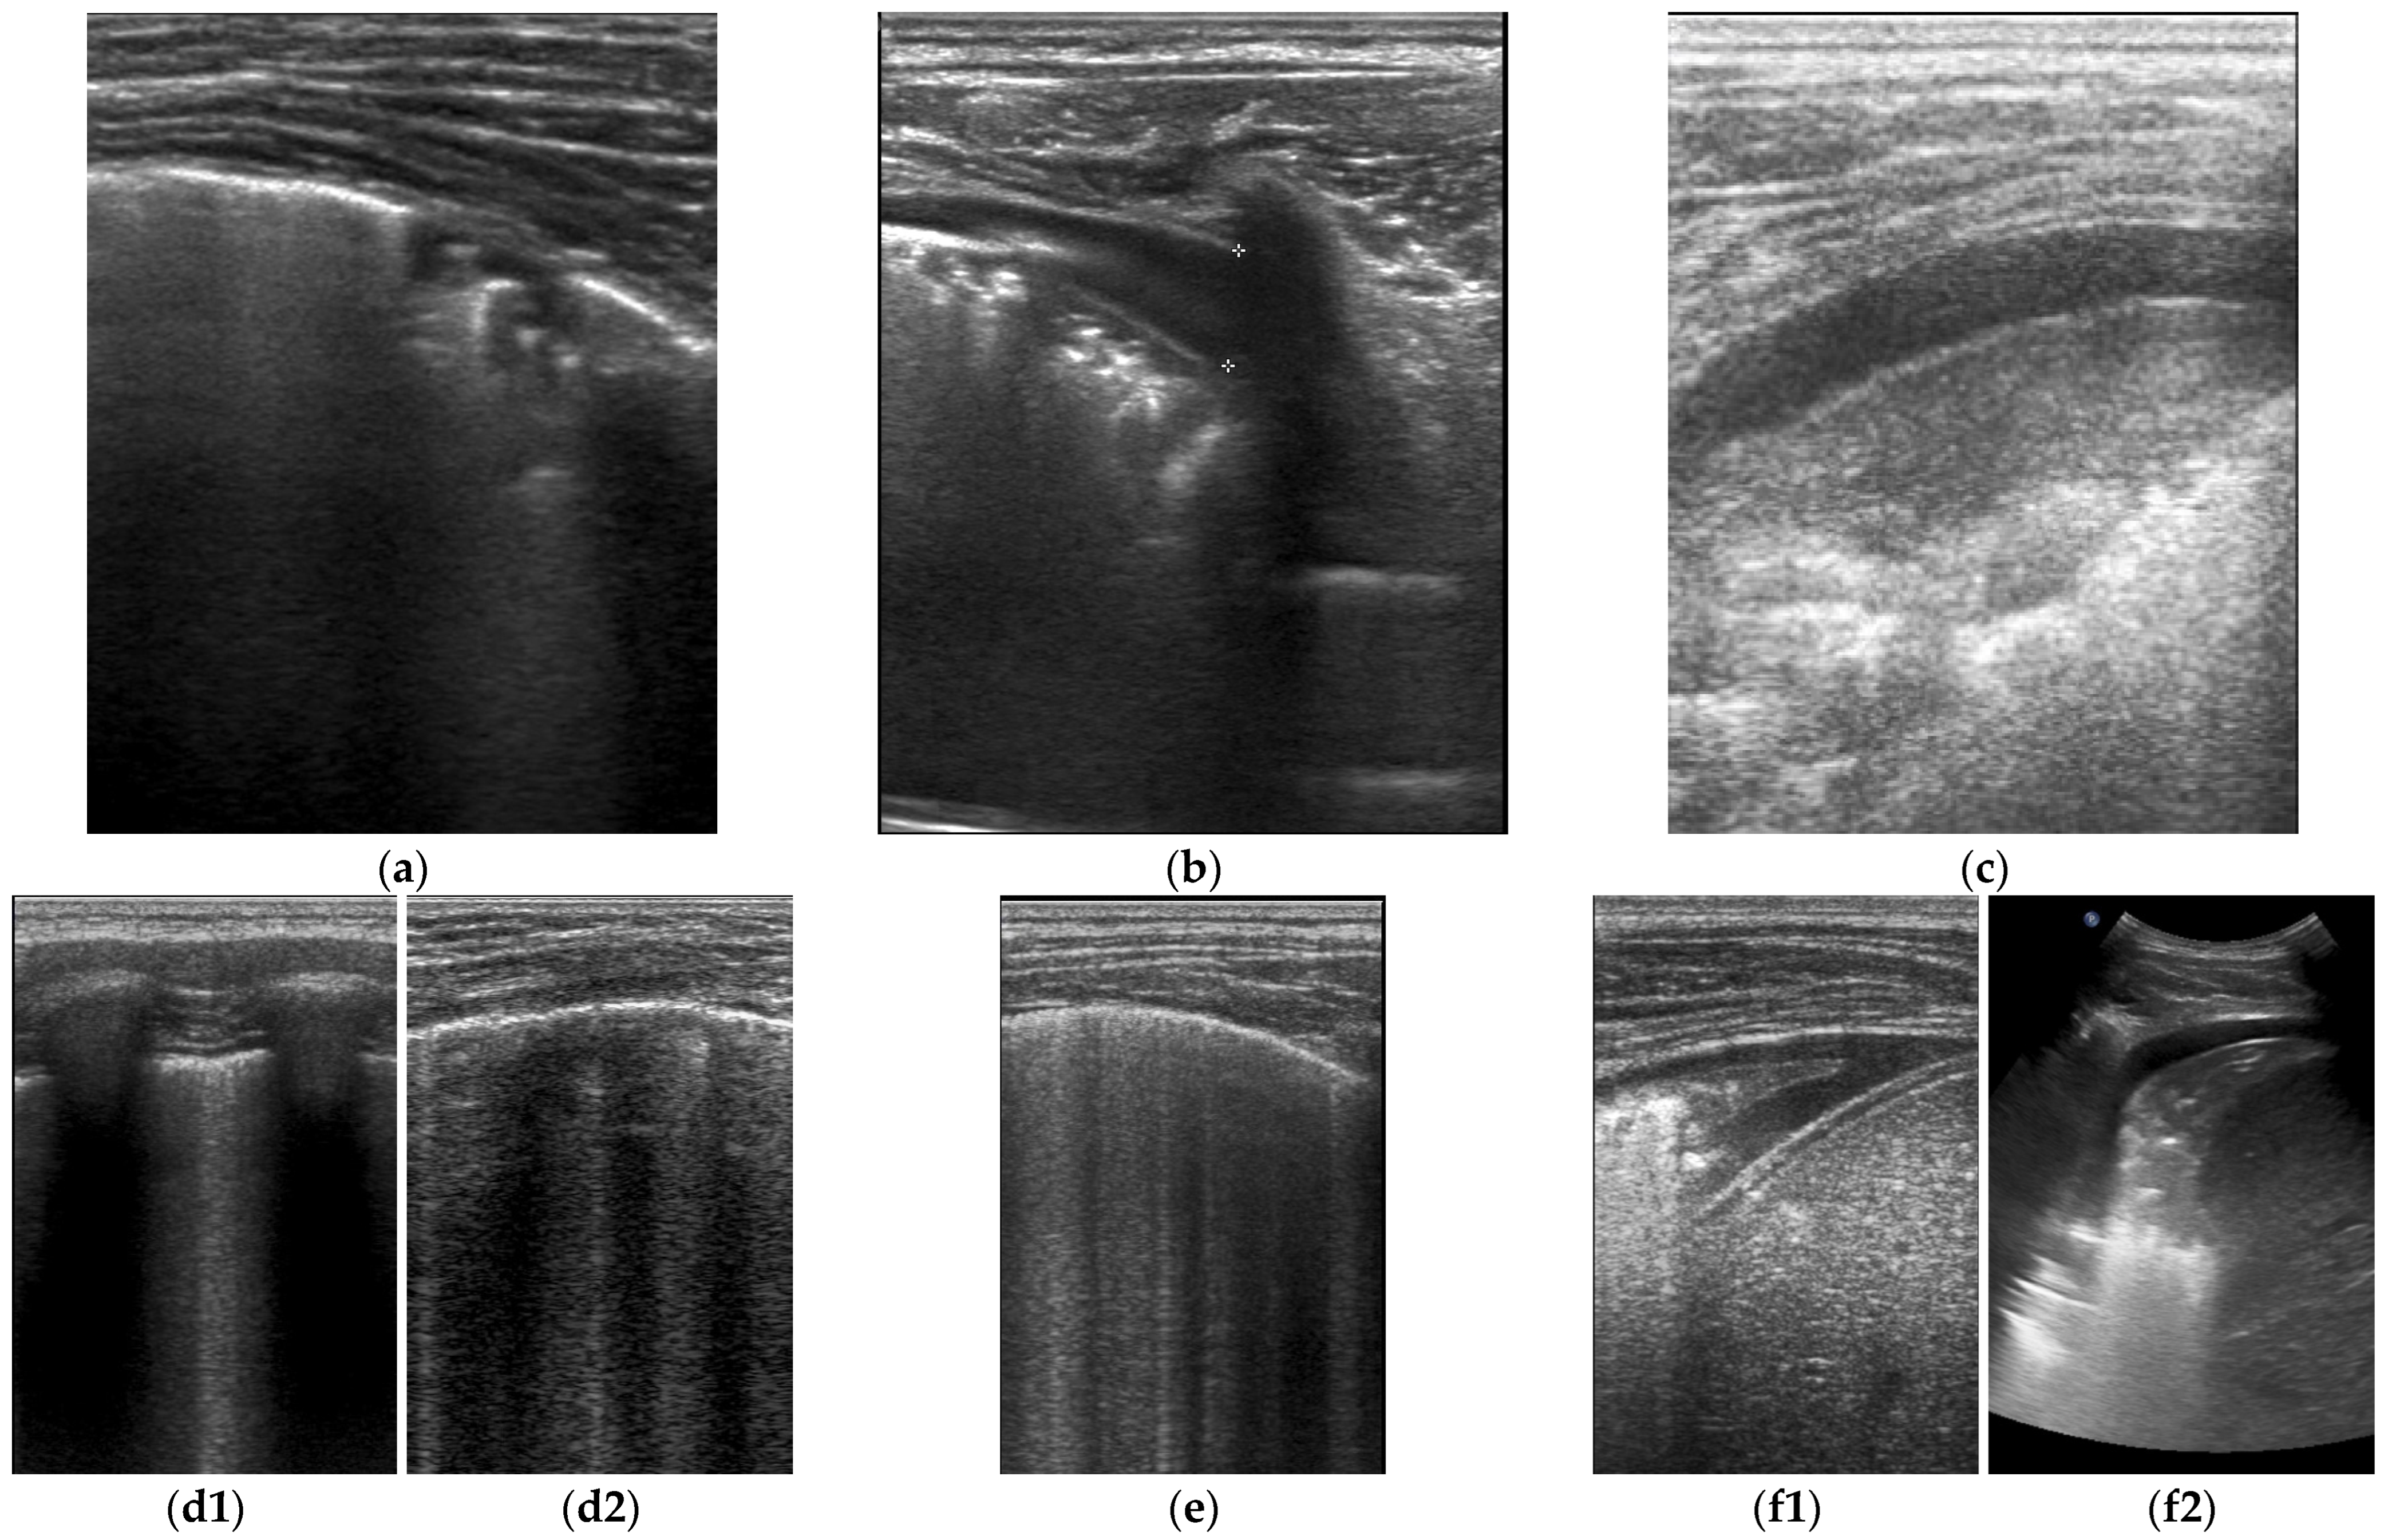

- Musolino, A.M.; Tomà, P.; De Rose, C.; Pitaro, E.; Boccuzzi, E.; De Santis, R.; Morello, R.; Supino, M.C.; Villani, A.; Valentini, P.; et al. Ten Years of Pediatric Lung Ultrasound: A Narrative Review. Front. Physiol. 2022, 12, 721951. [Google Scholar] [CrossRef]

- Jaworska, J.; Buda, N.; Ciuca, I.M.; Dong, Y.; Fang, C.; Feldkamp, A.; Jüngert, J.; Kosiak, W.; Mentzel, H.J.; Pienar, C.; et al. Ultrasound of the pleura in children, WFUMB review paper. Med. Ultrason. 2021, 23, 339–347. [Google Scholar] [CrossRef] [PubMed]

- Dietrich, C.F.; Buda, N.; Ciuca, I.M.; Dong, Y.; Fang, C.; Feldkamp, A.; Jüngert, J.; Kosiak, W.; Mentzel, H.J.; Pienar, C.; et al. Lung ultrasound in children, WFUMB review paper (part 2). Med. Ultrason. 2021, 23, 443–452. [Google Scholar] [CrossRef] [PubMed]

- Dietrich, C.F.; Mathis, G.; Blaivas, M.; Volpicelli, G.; Seibel, A.; Atkinson, N.S.; Cui, X.W.; Mei, F.; Schreiber-Dietrich, D.; Yi, D. Lung artefacts and their use. Med. Ultrason. 2016, 18, 488–499. [Google Scholar] [CrossRef] [PubMed]

- Volpicelli, G.; Elbarbary, M.; Blaivas, M.; Lichtenstein, D.A.; Mathis, G.; Kirkpatrick, A.W.; Melniker, L.; Gargani, L.; Noble, V.E.; Via, G.; et al. International Liaison Committee on Lung Ultrasound (ILC-LUS) for International Consensus Conference on Lung Ultrasound (ICC-LUS). International evidencebased recommendations for point-of-care lung ultrasound. Intensive Care Med. 2012, 38, 577–591. [Google Scholar] [CrossRef] [PubMed]